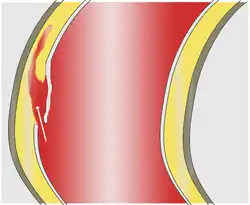

1 Adventitia – 2 Media – 3 Intima

Die Gefäßwand der Aorta besteht, von außen nach innen betrachtet, aus den drei Schichten Adventitia (Tunica adventitia), Media (Tunica media) und Intima (Tunica intima). Wenn die elastischen oder muskulären Anteile der Media geschwächt sind, kann sich eine Blutung dort mehr oder weniger ungehindert ausdehnen und zu einer Aufspaltung (Dissektion) der Gefäßwand zwischen Intima und Adventitia führen.

Als unmittelbare Auslöser der Dissektion werden zwei verschiedene Mechanismen diskutiert. Am häufigsten kommt es zunächst zu einem Einriss der Intima, der dem Blutstrom einen Zugang zur Media öffnet. Durch diese Öffnung (engl.: entry) presst der arterielle Blutdruck das Blut zwischen Intima und Adventitia, wo es sich meist in Längsrichtung des Gefäßes weiter ausdehnt und einen künstlichen Raum („falsches Lumen“) schafft.

Seltener scheint eine Blutung in die Media als primäres Ereignis zu einem zunächst kleinen Bluterguss (Hämatom) zu führen. Sie stammt aus den Versorgungsgefäßen (Vasa vasorum, vgl. Gefäß) der Aorta und verschafft sich in vielen Fällen erst sekundär Zugang zum Gefäßlumen, wenn der Druck des Blutergusses die Intima zerreißt. Einige dieser Hämatome sind auf die Gefäßwand beschränkt und bleiben ohne Verbindung zum Blutstrom in der Aorta (intramurales Hämatom).